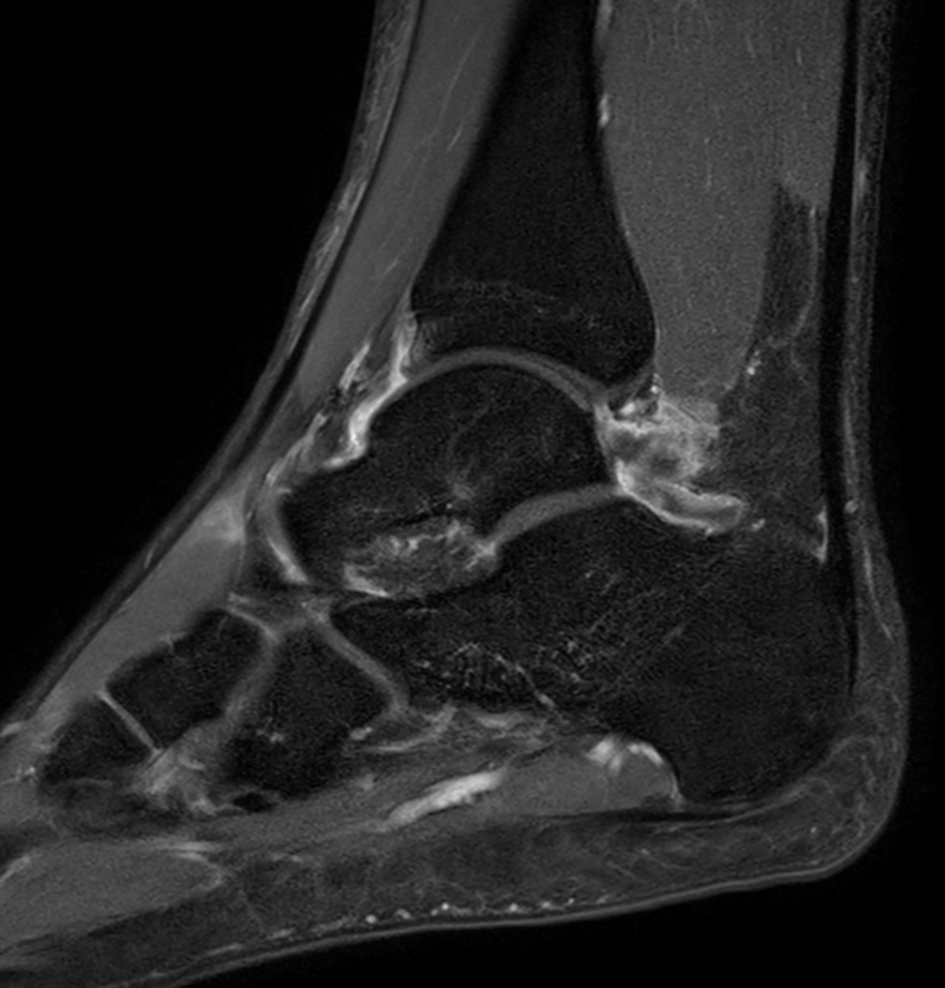

High resolution Ankle imaging in short scan times

Spital Uster, Switzerland

Sagittal PDw TSE - mDIXON XD (In Phase)

Sagittal PDw TSE - mDIXON XD (Water only)

Sagittal T1w TSE